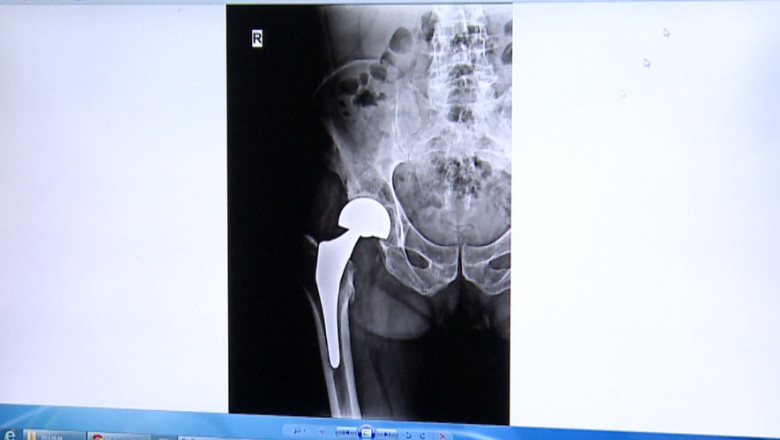

Medicii spun că lista de aşteptare se întinde pe mai bine de jumătate de an pentru că anul acesta, nu pot face mai mult de 15 intervenţii pe lună, faţă de 30 câte se realizau anul trecut. În plus, a crescut foarte mult numărul de cazuri. Săptămânal, la spital ajung câte 10 vârstnici cu fracturi grave. "Speranţa de viaţă crescând avem tot mai mulţi vârstnici, avem tot mai mulţi pacienţi cu boli degenerative. Sigur că ar trebui mai mulţi bani şi pentru program," a spus Paul Sîrbu, medic ortoped.

Conducerea Spitalului de Recuperare din Iaşi speră ca Ministerul Sănătăţii să suplimenteze suma alocată. "S-au făcut nenumărate solicitări şi ceea ce am reuşit este ca suma alocată să ne fie alocată în această lună întreaga sumă, toate creditele să putem opera pacienţii care sunt incluşi pe listă urmând ca la o eventuală rectificare bugetară să ne mai fie alocate sume suplimentare," a declarat Carmen Cumpăt, managerul Spitalului de Recuperare Iaşi.